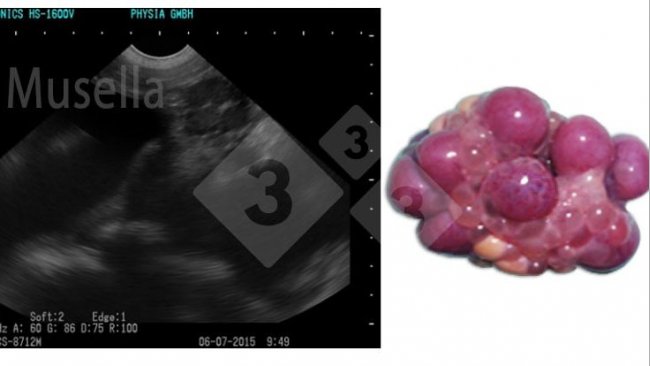

Se puede utilizar la ecografía para visualizar las estructuras ováricas, evaluar el estado puberal y diagnosticar patologías ováricas.